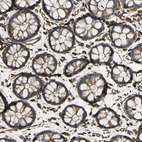

Immunohistochemical staining of human tonsil shows very strong cytoplasmic positivity in non-germinal center cells.